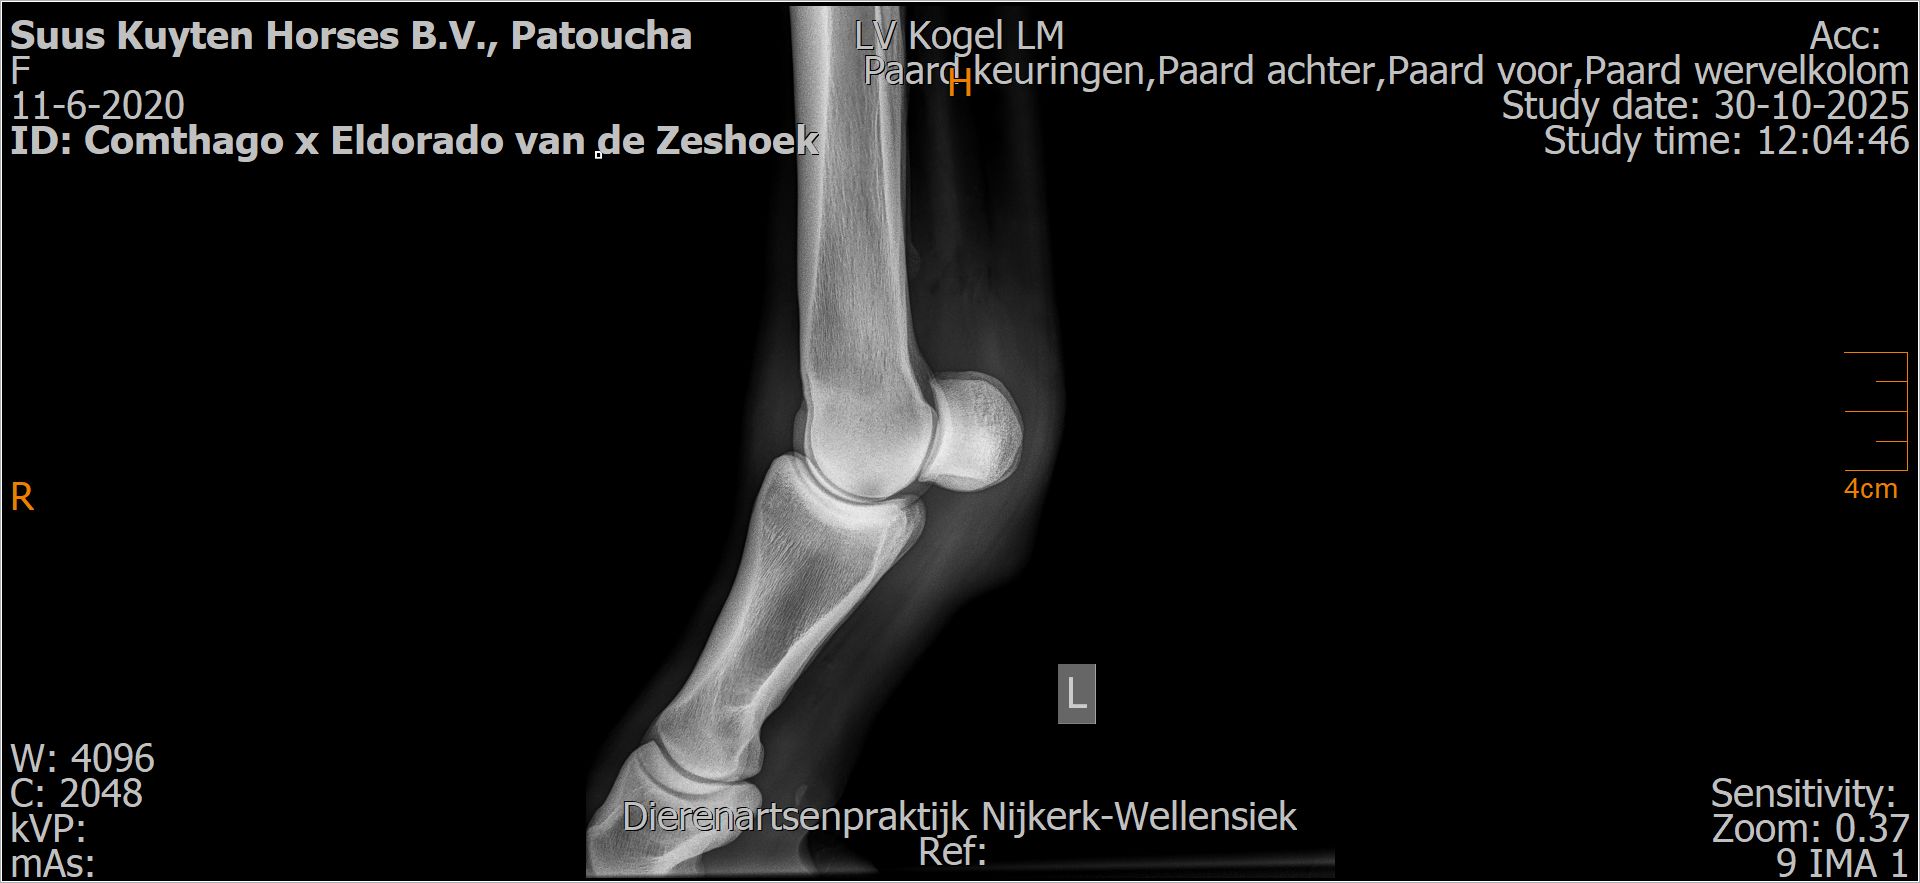

Patoucha

Leeftijd:

7

Röntgenfoto’s